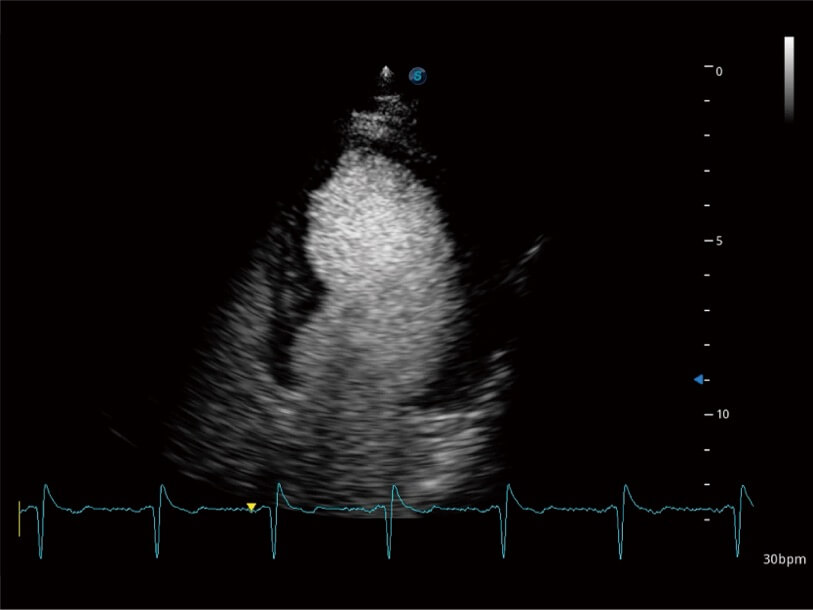

Ausgestattet mit dem gesamten Sortiment an Phased-Array-Schallköpfen von SonoScape (S1-5, 7P-A, 8P1), hochentwickelter Verarbeitungstechnologie und modernsten kardiologischen Tools bietet die ProPet-Serie Tierärzten eine umfassende ABklärung der Herz- und Myokardfunktionen.

Erfasst multiple dynamische Bilder in Ruhe und nach Belastung für den Vergleich Seite bei Seite. Für eine weitergehende effektive Abklärung der Vitalität des Herzmuskels werden professionelle Scores und Berichte zur Wandbewegung des Tieres bereitgestellt.